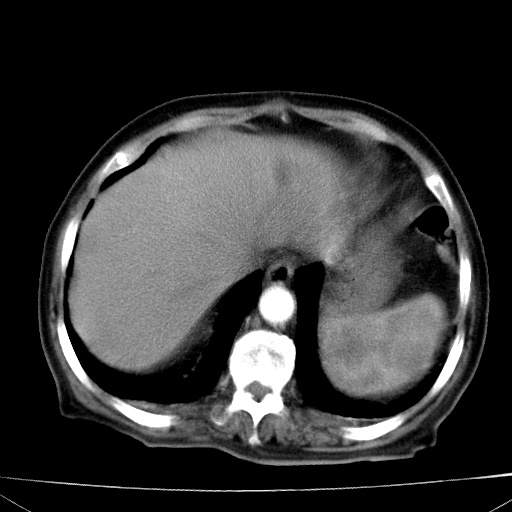

网站人气太旺!昨天的帖子就沉到海底,只好再发贴!ct18338:女 78岁,肝胆病变,已增强,再会诊!原帖链接:http://www.radida.com/bbs/forum.php?mod=viewthread&tid=50032

1)考虑胆囊癌侵犯肝脏并肝门区、腹膜后及右侧膈角后淋巴结转移。2)肝左叶近肝顶部囊肿。3)肝左叶肝内胆管结石。4)左肾近下极囊肿。